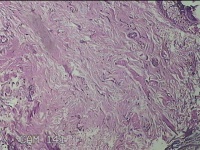

右颈部皮肤肿物

性别

女

年龄

29岁

临床诊断

纤维瘤

一般病史

右颈部皮肤起肿物10年左右。

标本名称

大体所见

灰白暗红色肿物0.3x0.2x0.1cm一个,表面光滑。